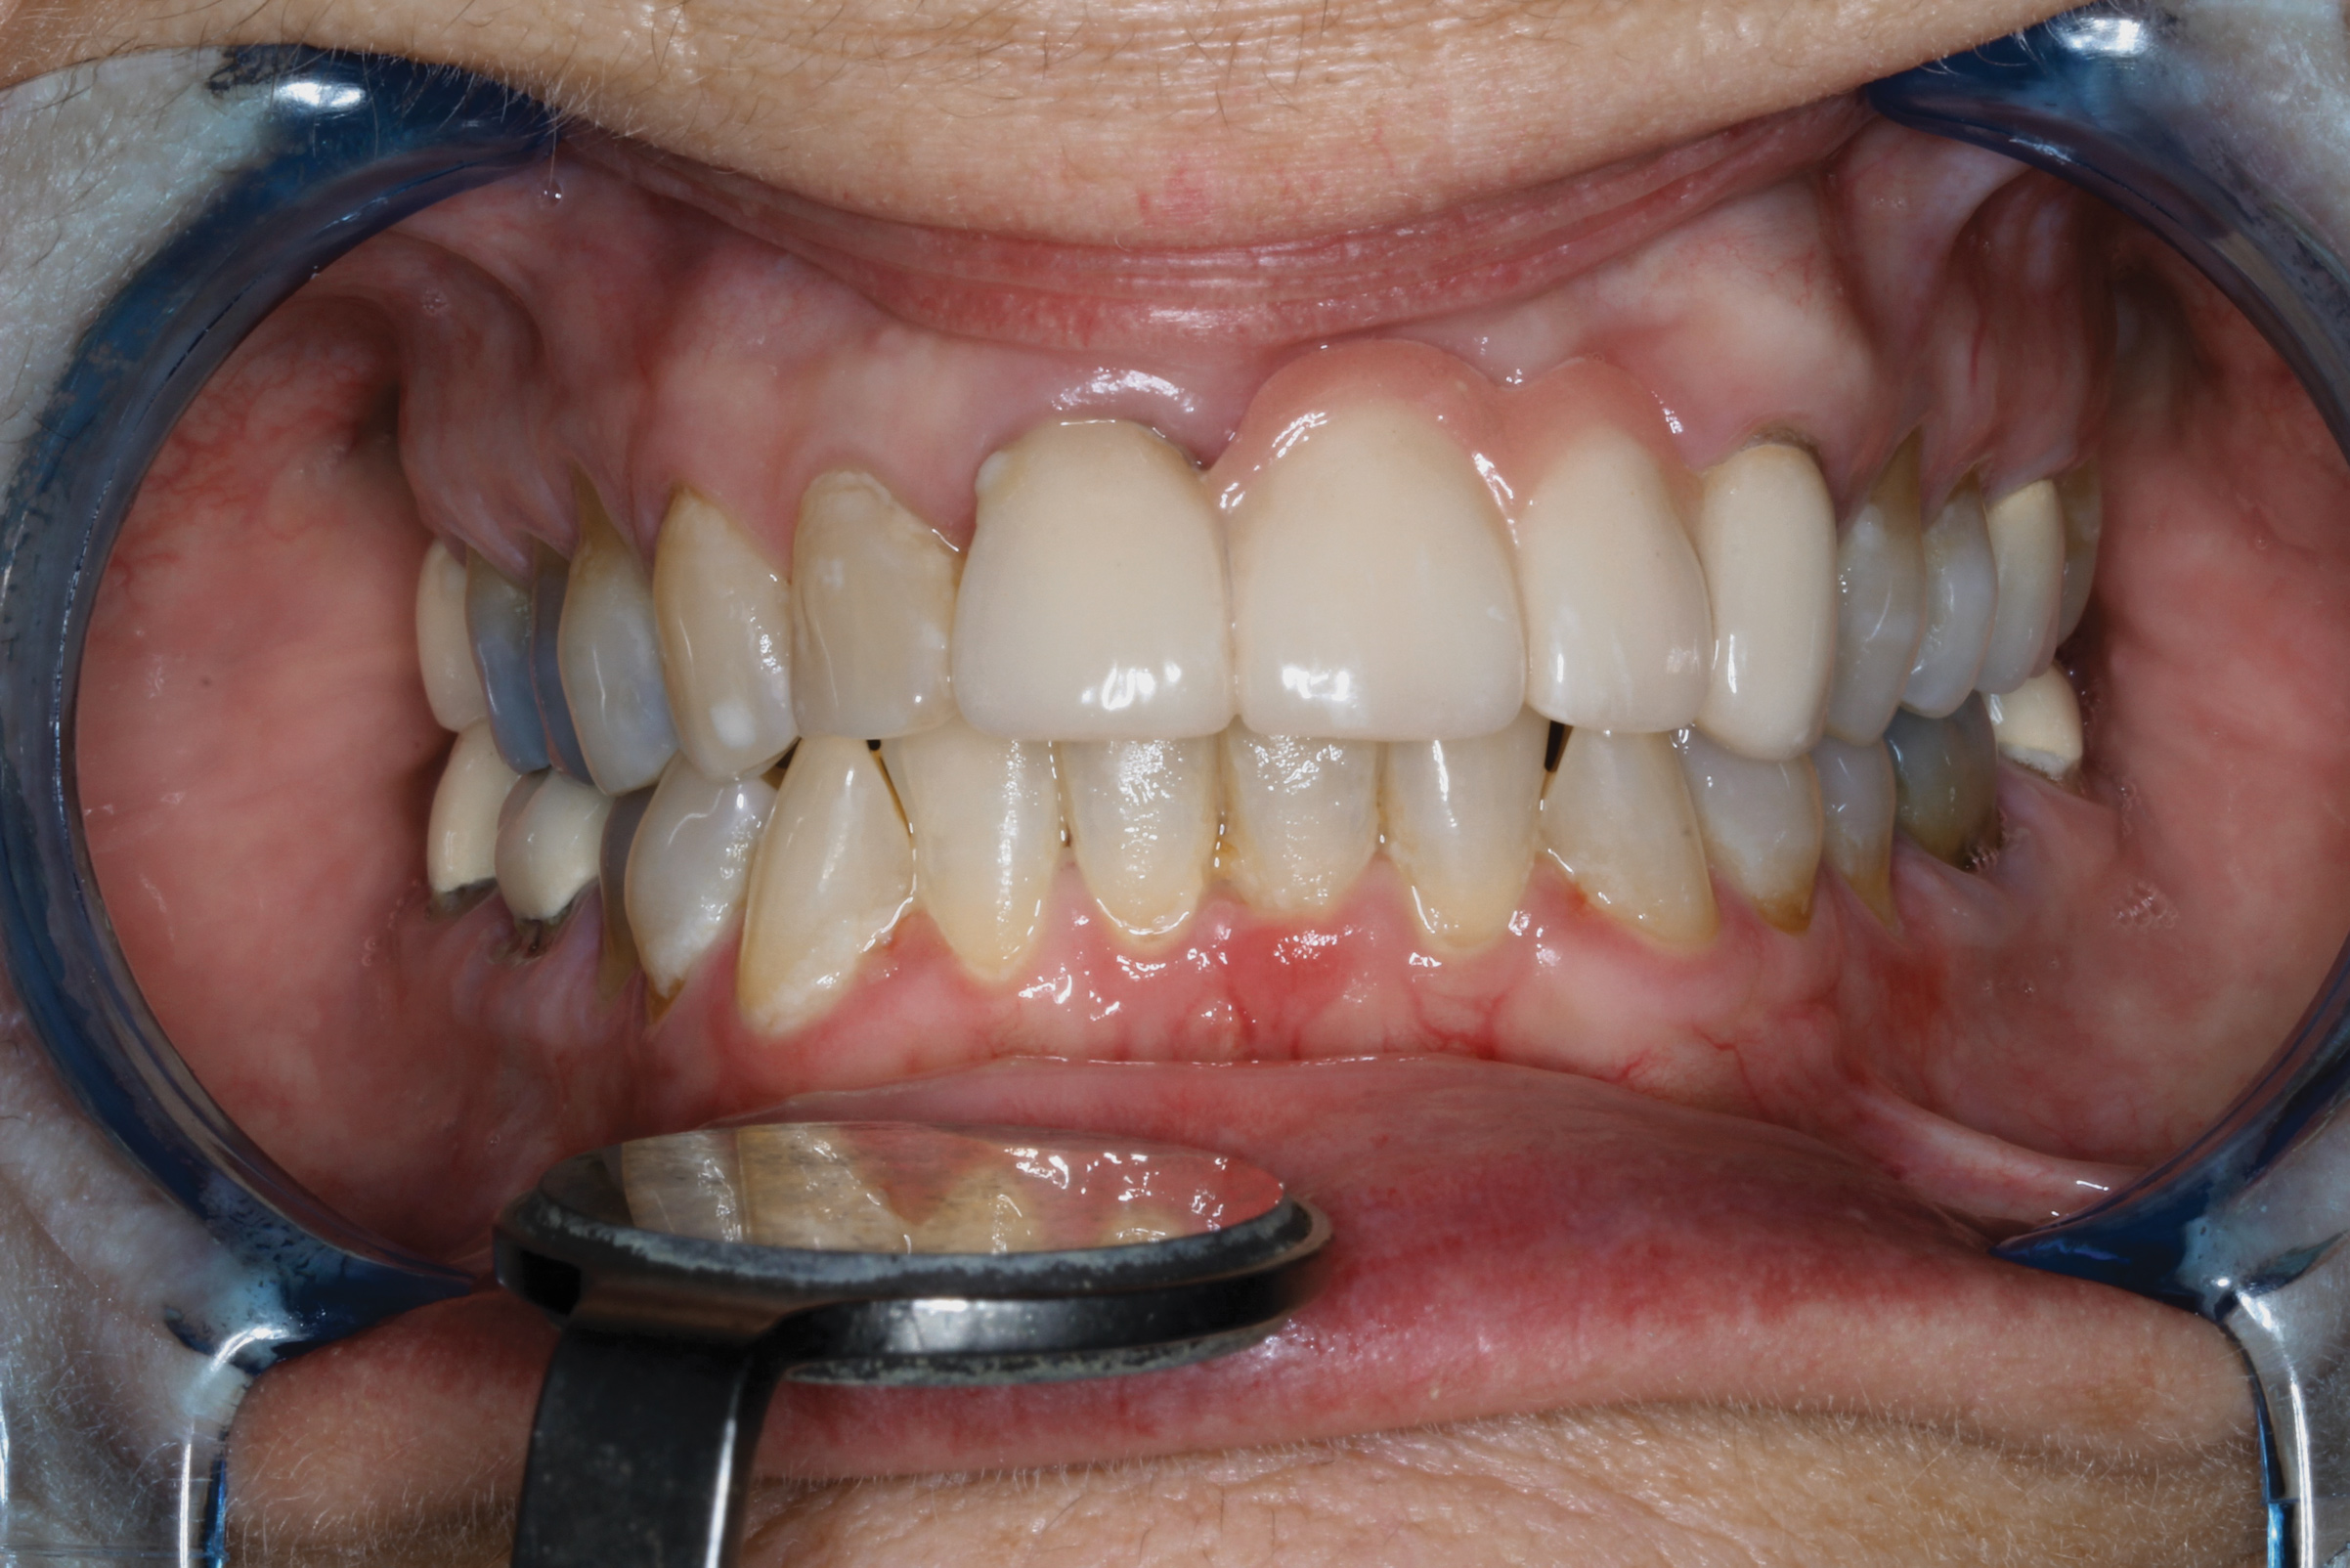

Fig 7. Seibert Class I defect in teeth Nos. 10 and 11 with Miller Class I to II recession on multiple teeth (Fig 7). A tuberosity CTG was used to treat the edentulous area at Nos. 10 and 11 and the periodontal recession on teeth Nos. 7 and 9. Allograft material was used to treat the other areas of periodontal recession. The final esthetic restorative treatment was completed with crowns on all upper teeth except for a bridge from Nos. 8 through 12 with ovate pontics in Nos. 10 and 11 (Fig 8). Note a keloid-like appearance was evident over teeth Nos. 7 and 9 due to ineffective trimming of the grafts (restorative treatment completed by Todd D. Gruen, DDS).

Figure 7

Fig 8. Seibert Class I defect in teeth Nos. 10 and 11 with Miller Class I to II recession on multiple teeth (Fig 7). A tuberosity CTG was used to treat the edentulous area at Nos. 10 and 11 and the periodontal recession on teeth Nos. 7 and 9. Allograft material was used to treat the other areas of periodontal recession. The final esthetic restorative treatment was completed with crowns on all upper teeth except for a bridge from Nos. 8 through 12 with ovate pontics in Nos. 10 and 11 (Fig 8). Note a keloid-like appearance was evident over teeth Nos. 7 and 9 due to ineffective trimming of the grafts (restorative treatment completed by Todd D. Gruen, DDS).

Figure 8

If insufficient tissue is harvested from the tuberosity for multiple-tooth CTG procedures, the addition of other graft materials may allow multiple teeth to be grafted in one treatment. In these situations, for higher predictability, use of autograft tissue (perhaps from the tuberosity) is suggested in the worst areas of recession and other graft materials (eg, allograft CT or membranes) would be used for augmentation in the less involved areas of periodontal recession (Figure 7 and Figure 8).

Having used tuberosity CT for nearly 20 years when performing a CTG for root coverage or soft-tissue ridge augmentation, the authors consider the tuberosity their first choice for the graft material, followed by allograft materials and/or membranes, and, finally, palatal tissue. However, if a palatal flap is elevated for any reason, and a CTG is needed elsewhere, the palate CT should also be considered for grafting. For root coverage on multiple teeth or soft-tissue ridge defects, the tuberosity CTG can be used individually or combined with allograft, xenograft, or autograft (palate or retromolar) tissues (Figure 8). Additionally, the authors have observed that the tuberosity is an excellent source for CTG for pre-adolescent patients and removes excess tissue thickness over unerupted second molars and aids in their eruption.